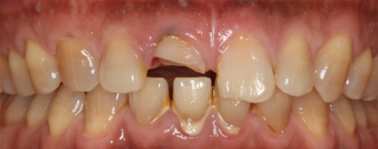

前歯が割れてしまってインプラントをご希望で来院された患者様です。

前歯に亀裂が入ってしまっており、抜歯後、インプラント治療を行いました。

非常に審美的な治療が出来ました。

当院では難しい前歯のインプラントも違和感なくきれいに処置することが出来ます。